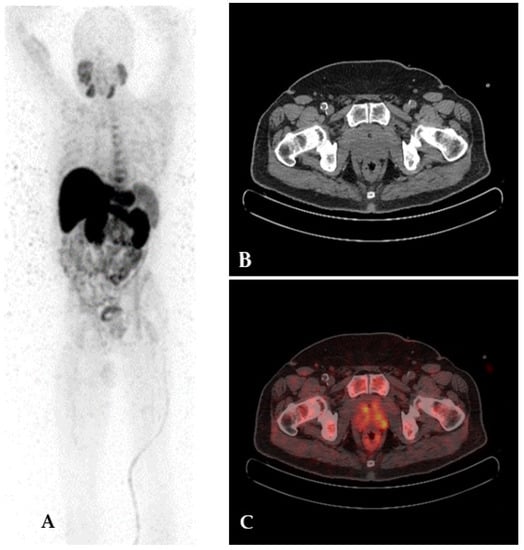

4.3. Prostate-Specific Membrane Antigen

- Fendler, W.P.; Eiber, M.; Beheshti, M.; Bomanji, J.; Calais, J.; Ceci, F.; Cho, S.Y.; Fanti, S.; Giesel, F.L.; Goffin, K.; et al. PSMA PET/CT: Joint EANM Procedure Guideline/SNMMI Procedure Standard for Prostate Cancer Imaging 2.0. Eur. J. Nucl. Med. Mol. Imaging 2023, 50, 1466–1486. [Google Scholar] [CrossRef] [PubMed]

- Trabulsi, E.J.; Rumble, R.B.; Jadvar, H.; Hope, T.; Pomper, M.; Turkbey, B.; Rosenkrantz, A.B.; Verma, S.; Margolis, D.J.; Froemming, A.; et al. Optimum Imaging Strategies for Advanced Prostate Cancer: ASCO Guideline. J. Clin. Oncol. 2020, 30, 1963. [Google Scholar] [CrossRef] [PubMed]

- Chen, R.; Wang, Y.; Zhu, Y.; Shi, Y.; Xu, L.; Huang, G.; Liu, J. The Added Value of 18F-FDG PET/CT Compared with 68Ga-PSMA PET/CT in Patients with Castration-Resistant Prostate Cancer. J. Nucl. Med. 2022, 63, 69–75. [Google Scholar] [CrossRef]

- Kepenek, F.; Can, C.; Kömek, H.; Kaplan, İ.; Gündoğan, C.; Ebinç, S.; Güzel, Y.; Agüloglu, N.; Karaoglan, H.; Taşdemir, B. Combination of [68Ga]Ga-PSMA PET/CT and [18F]FDG PET/CT in Demonstrating Dedifferentiation in Castration-Resistant Prostate Cancer. Médecine Nucléaire 2023, 47, 193–199. [Google Scholar] [CrossRef]